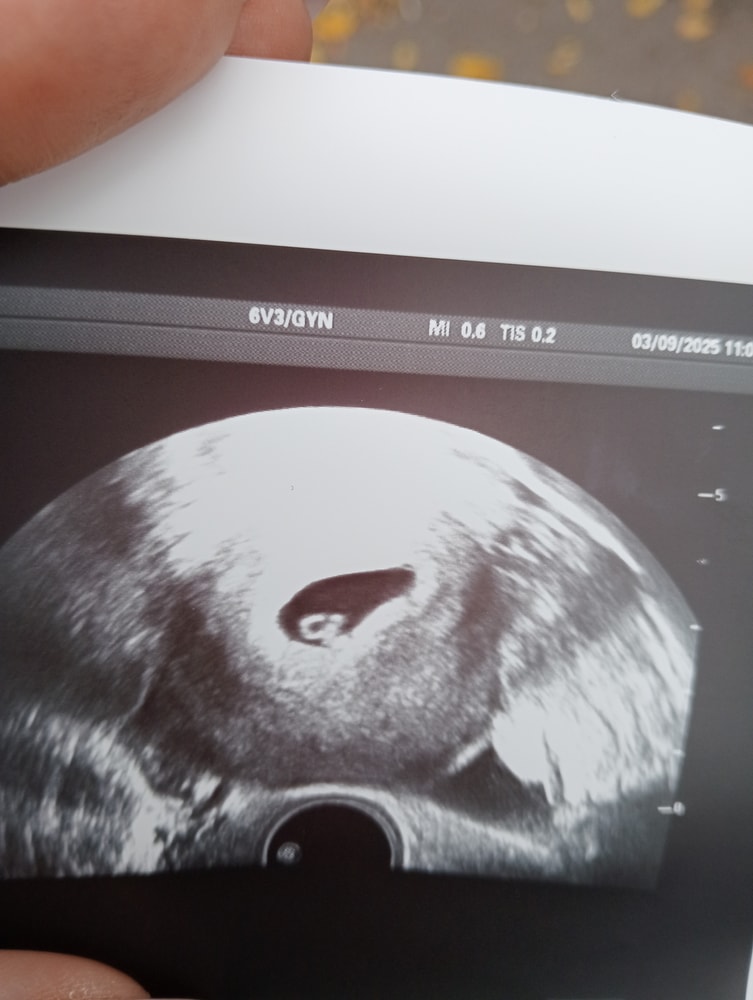

26 дпп. Первое УЗИ

Ну наконец то я первый раз после подсадки сходила на УЗИ к своему репродуктологу, она сказала раньше смысла нет идти, если ничего не беспокоит и хгч отлично растет. Показала эмбриончик, сердцебиение, все замерила, рассказала, показала, дала фото на память и написала назначения, я на згт , так что принимаю много всего и постепенно буду снижать. И так динамика ХГЧ, кому интересно:

7дпп-82

9дпп-239

11дпп-526

17дпп-7282